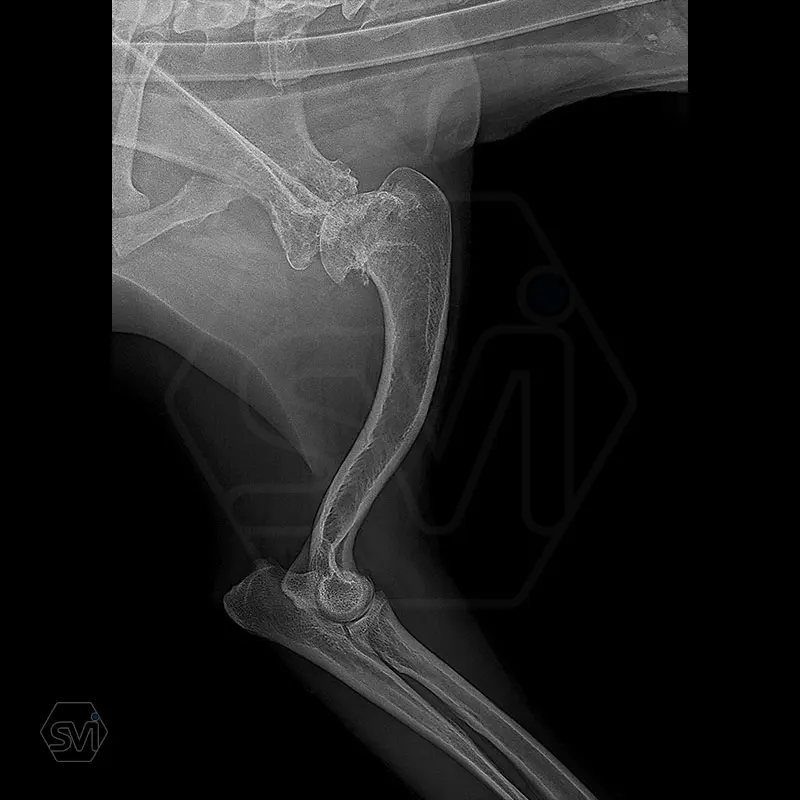

In our case, we created a shoulder arthrodesis on an 11-year-old 16kg female beagle dog with a 2.7 SOP-LC system and 4-4 clamps. The dog developed chronic arthritis and arthrosis, the biopsy did not confirm a tumor, only chronic inflammation.